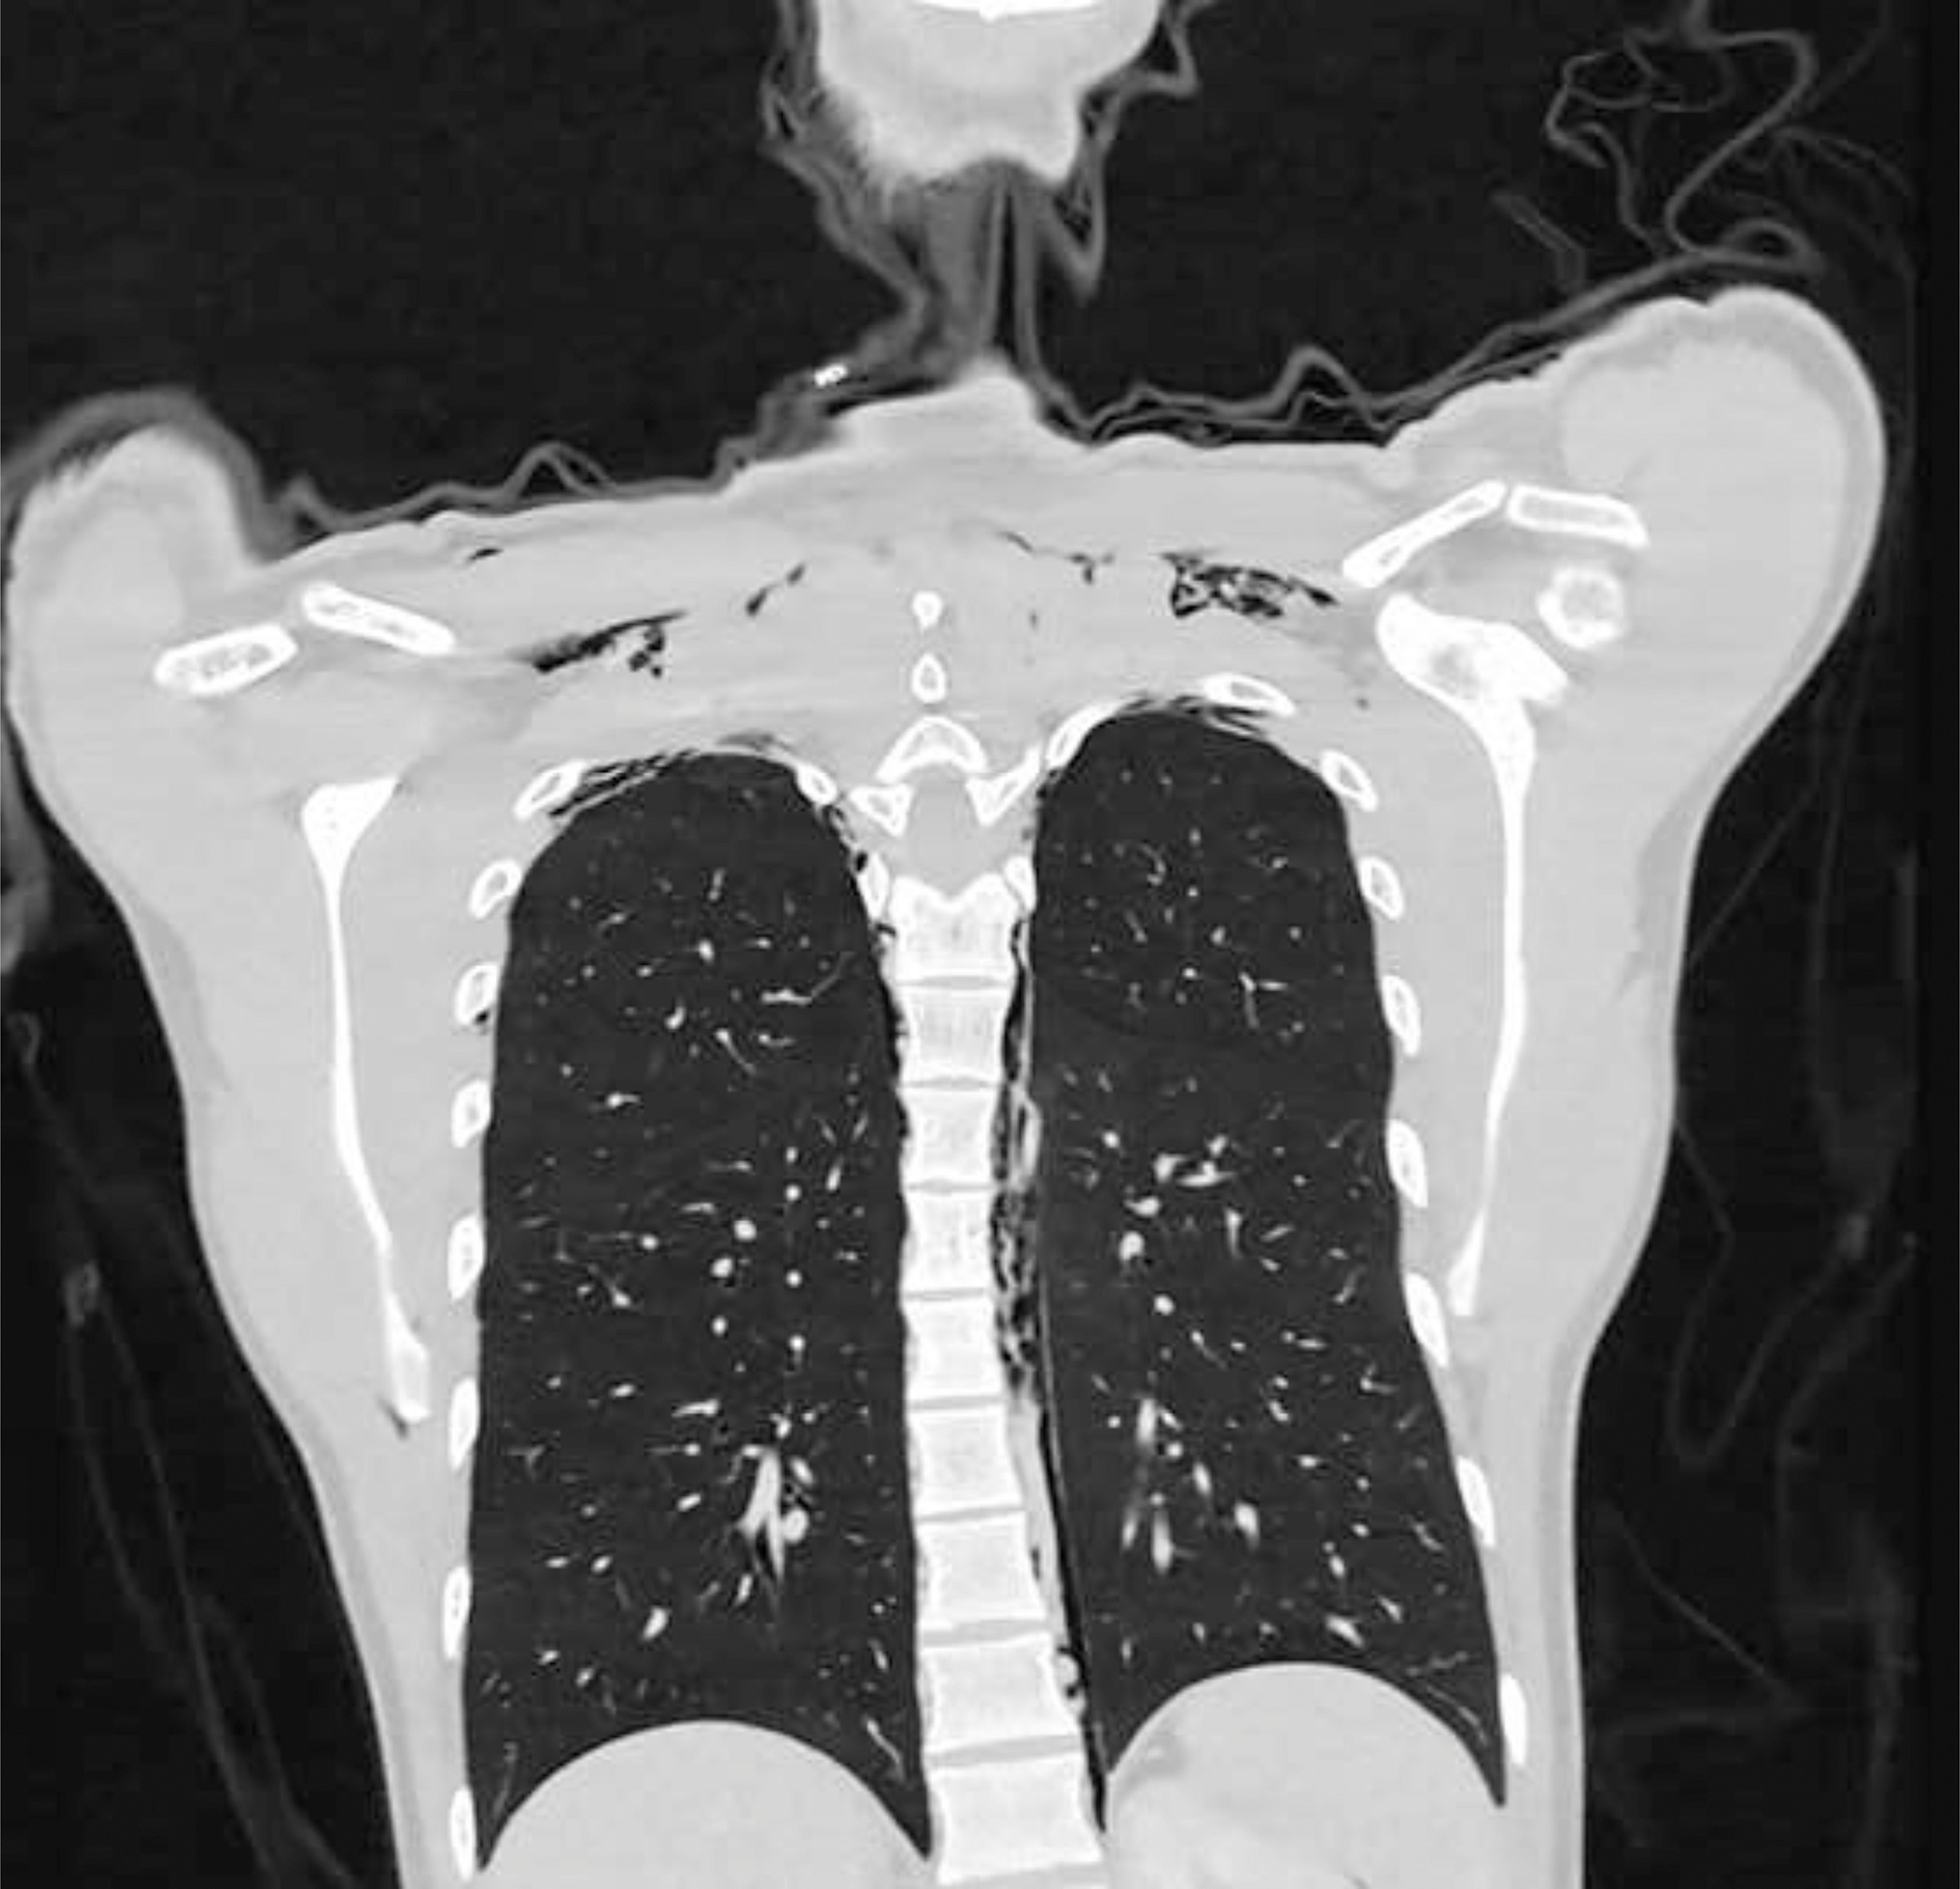

Shocking x-ray images from the case shed light upon the most severe case of pneumomediastinum which is the medical term ‘benign disease’.

Here is where the air is known to leak out from the lung and slowly becomes dislodged painfully between the rib cage.

Not only did the man’s face swell up to a severe extent, but doctors could also hear awfully painful ‘crunching’ noises coming from his neck and leading down to his elbow region. And that’s when a confirmation regarding his medical condition was made as the air was seen to be trapped towards the bases of the skull.